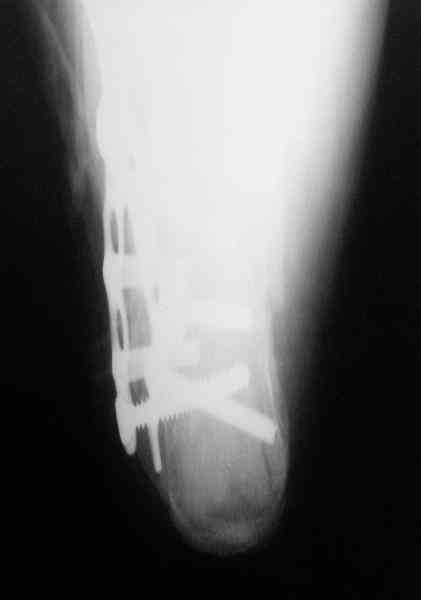

Re: Перелом пяточной кости

Открытый и закрытый способы лечения.